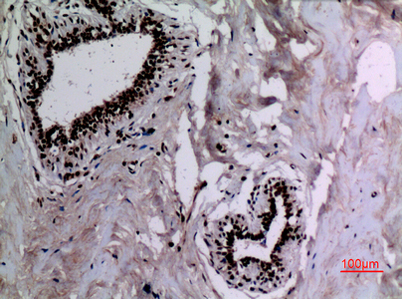

Product name: HSP 90 (Acetyl Lys292/284) rabbit pAb

Dilutions: Western Blot: 1/500 - 1/2000. IHC-p: 1:100-300 ELISA: 1/20000. Not yet tested in other applications.

Immunogen: The antiserum was produced against synthesized Acetyl-peptide derived from human HSP90A/B around the Acetylation site of Lys292/284. AA range:251-300

Cellular localization: Nucleus . Cytoplasm . Melanosome . Cell membrane . Mitochondrion . Identified by mass spectrometry in melanosome fractions from stage I to stage IV.

Background: The protein encoded by this gene is an inducible molecular chaperone that functions as a homodimer. The encoded protein aids in the proper folding of specific target proteins by use of an ATPase activity that is modulated by co-chaperones. Two transcript variants encoding different isoforms have been found for this gene. [provided by RefSeq, Jan 2012],